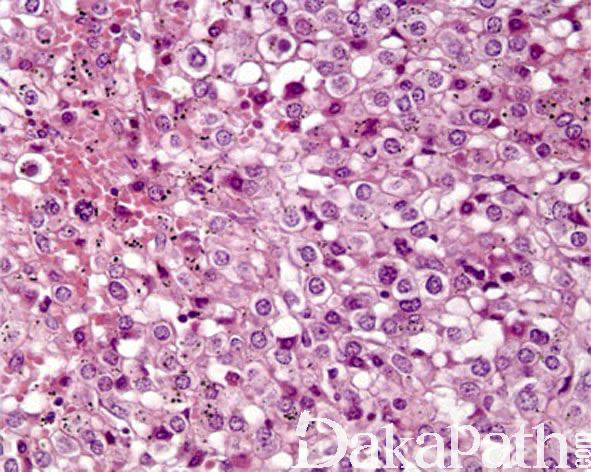

瘤细胞大小较一致,多角形或胖梭形,胞浆多少不等,弱嗜酸性,可见单个的中位核,核仁不明显,核分裂象罕见或缺如。偶见退行性变的核非典型性和局灶的坏死,与肿瘤的生物学行为无关。

肿瘤间质血管丰富,从大量的毛细血管到成簇的厚壁血管不等,后者常见管壁的玻璃样变性。